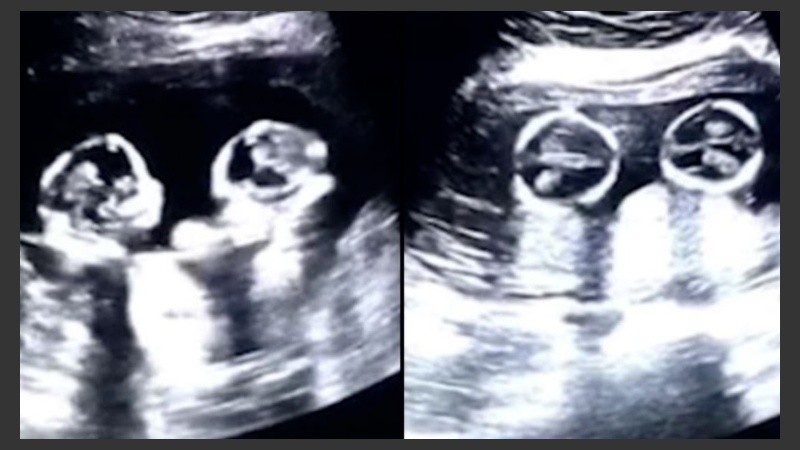

En las últimas horas, se viralizó el video de unas gemelas que –en apariencia– pelean en el útero de su madre mientras esta se realiza un control de embarazo en un centro de salud de Yinchuan, en China.

Atento al monitor del ultrasonido, el padre las capturó en pleno revuelo. Tanta es la agitación, que hasta parecen “golpes”.

La madre cursa un embarazo de cuatro meses. Y ambo fetos comparten el saco amniótico y la placenta, algo que sucede tan solo una vez en cada 60.000 casos.